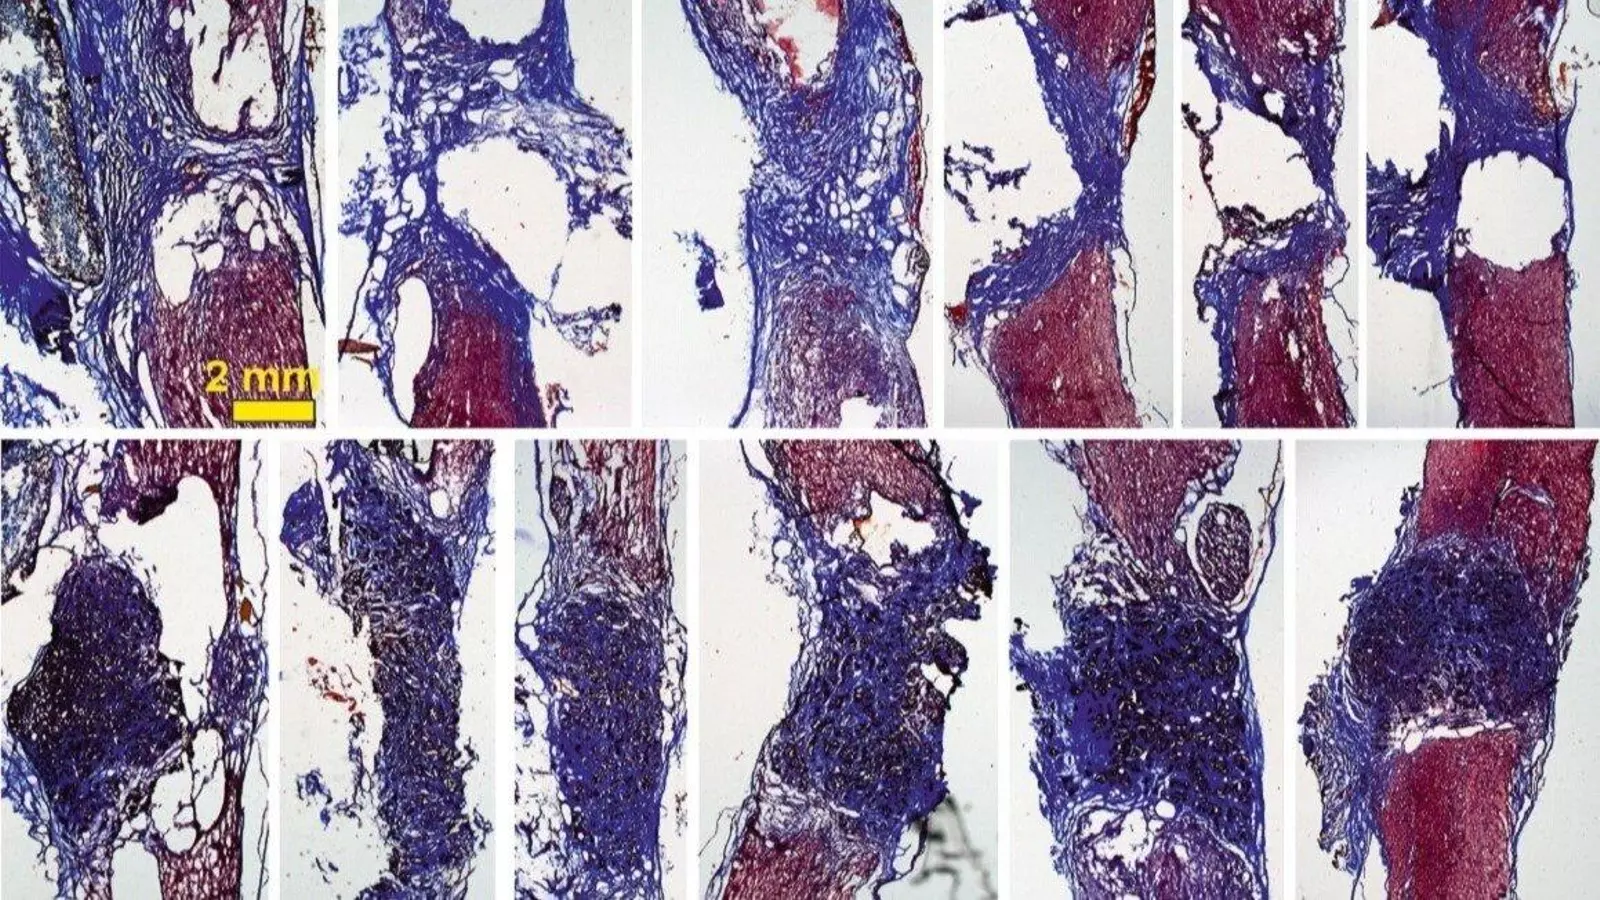

La investigadora explica que con esto se observa "cómo las neuronas que han sobrevivido en la zona alrededor de la lesión proyectan sus prolongaciones a través del `scaffold` y lo invaden en toda su extensión 3D". Todo esto, además, mejora con el tiempo: los resultados son incipientes tras 10 días de implante, pero son mucho más prometedores a los 4 meses.

"Nuestros `scaffolds` de óxido de grafeno reducido favorecen el crecimiento de vasos sanguíneos más abundantes y más grandes, y neuritas más abundantes, más largas y, además, distribuidas de manera más homogénea en el espacio de la lesión", ha manifestado Serrano.